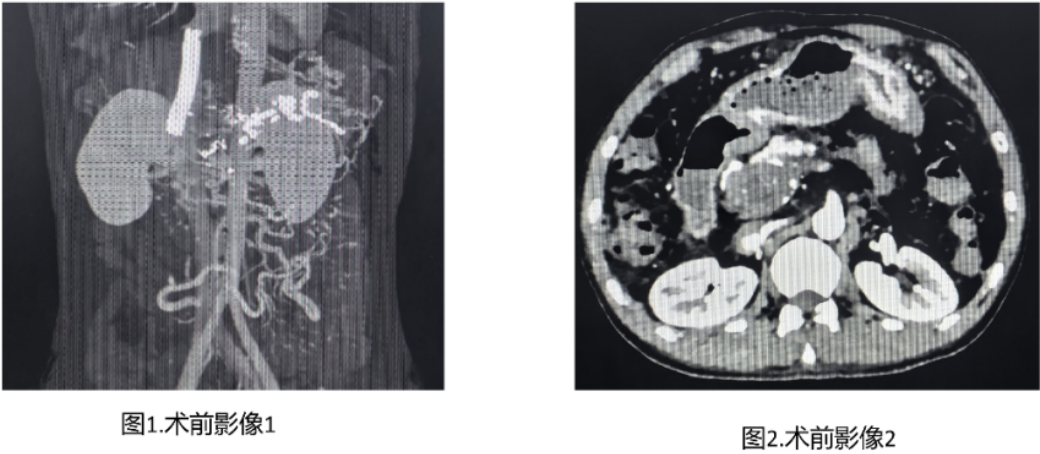

术前分析门静脉成像后发现:肠系膜上静脉侧支与下腔静脉间距达5.5cm,远超常规穿刺针长度;两者之间为完全血栓化的门静脉瘤,无肠管等重要结构——这恰恰为TEPS提供了理想解剖路径。经充分沟通与周密准备,介入血管科团队决定挑战这一高难度创新术式。